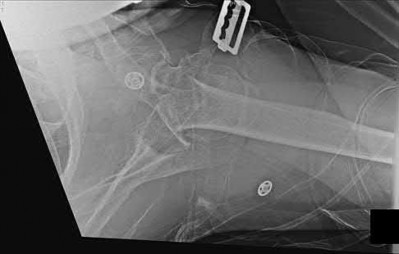

3. # Which of the following is not an appropriate implant for treatment of the fracture seen in Figure A?

1. Cephalomedullary nail

2. External fixation

3. Proximal femoral locking plate

4. 95 degree blade plate

5. Sliding hip screw Corrent answer: 5

The image shows a reverse obliquity intertrochanteric hip fracture.

According to the referenced article by Haidukewych et al, unstable peritrochanteric hip fractures have a worse outcome (failed in 9/16 cases) if treated with a sliding hip screw. Two additional factors that were found to have a strong correlation with postoperative failure (nonunion, loss of reduction) were poor reduction and poor implant placement. In this study, fixed angle devices were superior. Intramedullary fixation has the added advantage of a shorter lever arm and less potential for fracture collapse and limb shortening.

The IMN also acts as a medial buttress.

According to Sanders et al, the dynamic condylar screw (DCS) can also be used in subtrochanteric models, but should not be used if extensive comminution is seen, as they reported a high failure rate with DCS in these fractures if highly comminuted. They report a 77% overall union rate with this device.